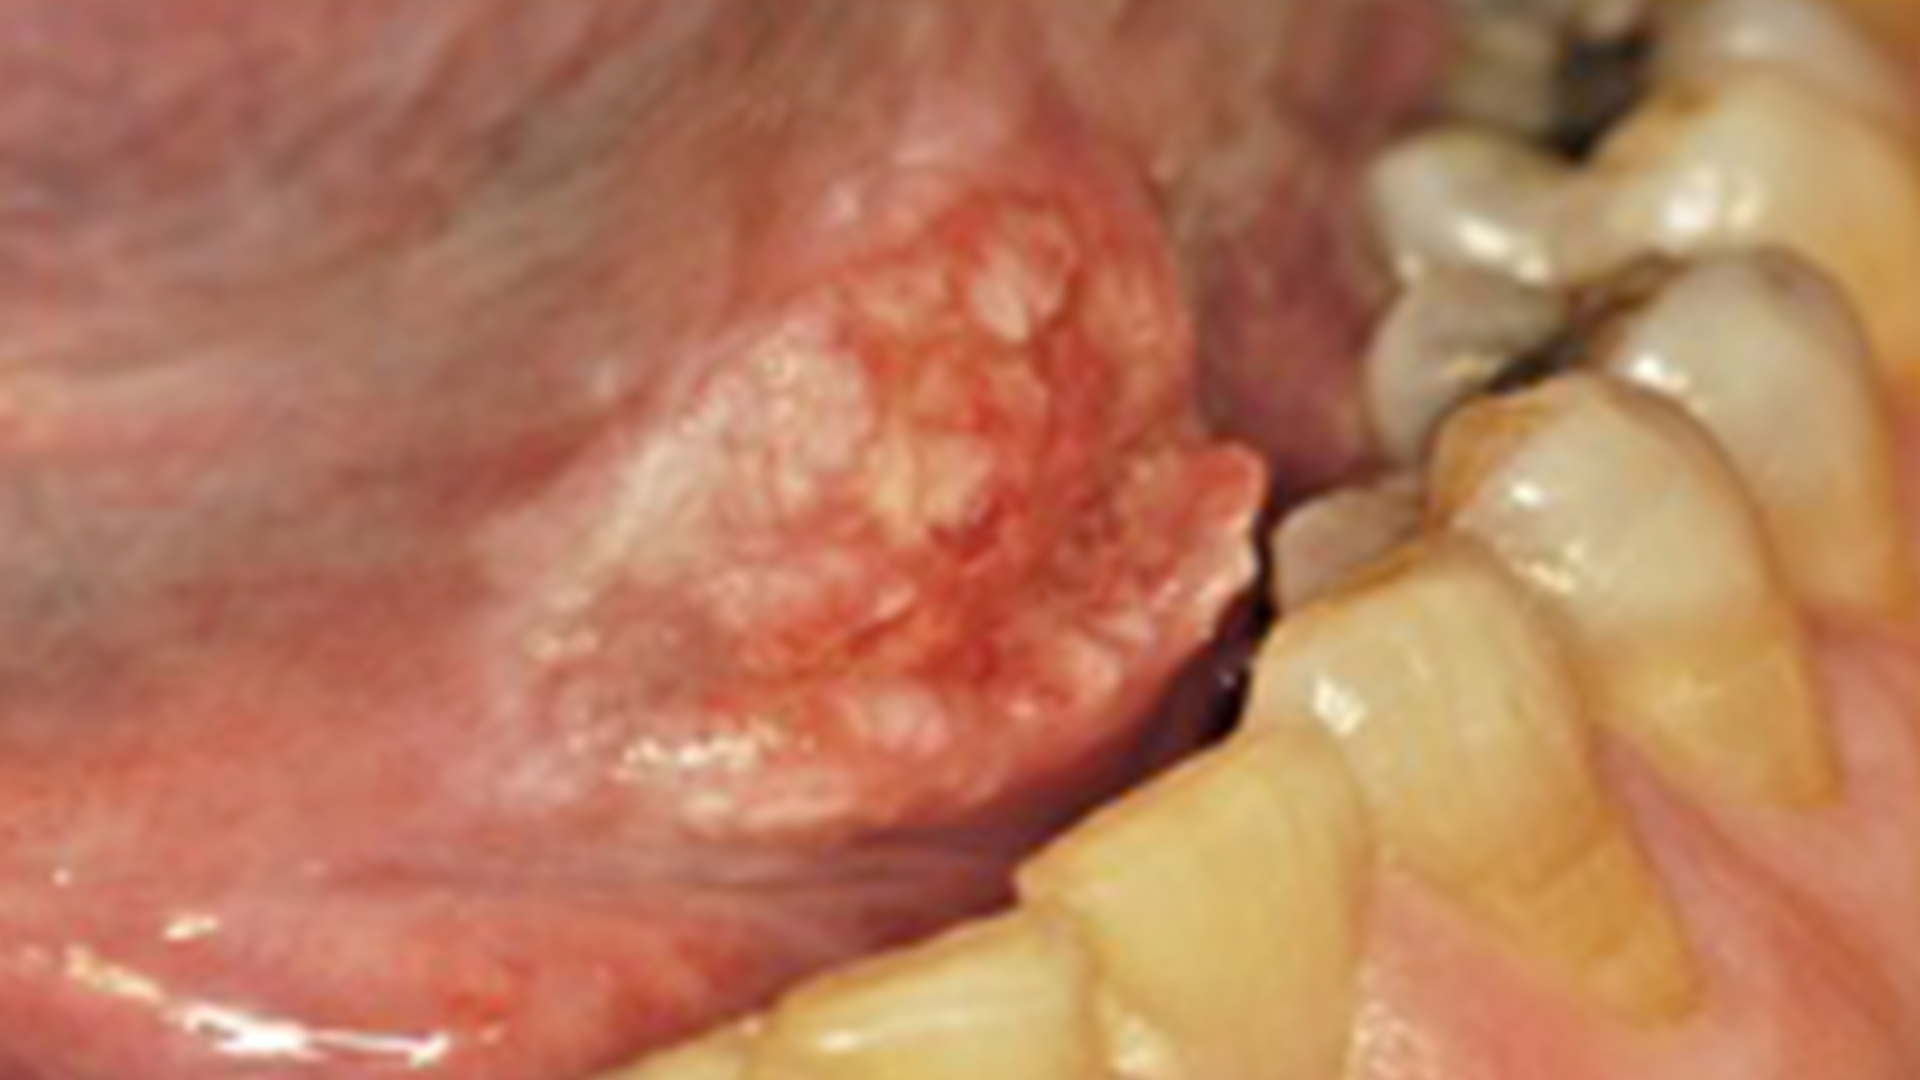

This two-part course will present the most common oral complications of cancer therapy and their impacts on dental care. Case Discussions are included to emphasize real-world application of the material in your practice. Part 1 presents the oral complications of conventional chemotherapy and newer targeted anticancer agents. Topics covered include oral mucositis, stomatitis, immunosuppression, oral infections, and other oral complications.

This is Part 2 of a two-part course on the oral complications of cancer therapy. Part 2 presents the oral complications of radiation therapy for head and neck cancer, as well as medication-related osteonecrosis of the jaw (MRONJ) in patients with cancer. Topics covered include radiation-induced oral mucositis, hyposalivation/xerostomia, oral infections, osteoradionecrosis, implications for dental care before and after radiation therapy, and MRONJ in oncology patients.